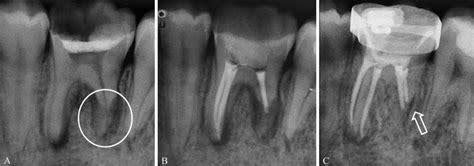

Root canal treatment involves removing the soft centre of the tooth—known as the pulp—by drilling a hole in the tooth, removing the infected pulp, disinfecting the root canals, clearing harmful bacteria, filling the inside of the tooth, and then crowning the tooth. The premise of root canal treatment is to save a tooth that is infected or decayed by removing the infected materials and thus avoid having it extracted.

The ugly part of root canals is what happens within these tubules when a tooth dies. As the living cells necrose (rot) within the central pulp chamber, their extensions also necrose within their tubules. Although root canal therapy should completely obliterate and fill the main pulp chamber, it is impossible to fill the millions of microscopic tubules.

An infected root canal can result from incomplete cleaning or sealing of the root canal system during treatment. This can easily occur due to the tooth’s complex anatomy, which has roots that contain main canals and thousands of tiny side canals. These canals house an intricate network of nerves that extend throughout the tooth.

During a root canal treatment, the dentist removes the nerve tissue from the main canals to alleviate pain and infection. However, the side canals are incredibly small and intricate, making it nearly impossible to completely remove all the nerve tissue. Thus, harmful infection-causing bacteria may remain inside the tooth, even after root canal treatment.